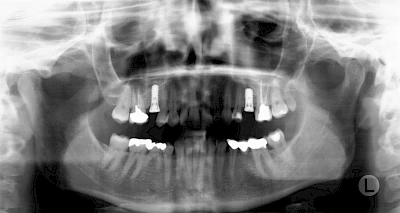

Fehlen einzelne Zähne und die Nachbarzähne sind unbeschadet oder gut zahnärztlich versorgt, werden immer häufiger Implantate gewählt, um die Lücken zu schließen. Auch bei größeren oder verteilten Lücken, wenn keine herausnehmbare Prothese gewünscht ist, werden Implantate für Kronen- bzw. Brückenversorgungen gesetzt. In Einzelfällen entscheiden sich sogar zahnlose Patienten für eine festsitzende Versorgung auf Implantaten.

In diesen Fällen kann die Planung mittels verschieden aufwendiger Röntgen-Techniken (Übersichtsaufnahme, DVT) ggf. unter Zuhilfenahme speziell angefertigter Planungsschablonen sinnvoll sein.